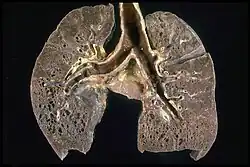

Da potenziell jedes Organ durch die Krankheit betroffen sein kann, richtet sich die Diagnostik nach der jeweiligen Beschwerdesymptomatik. Aufgrund der oft symptomlos verlaufenden Lymphknotenschwellungen wird die Sarkoidose nicht selten zufällig beim Röntgen-Thorax festgestellt. Je nach Befallsmuster und Zeichnung im Röntgenbild oder in der Computertomographie kann die pulmonale Sarkoidose in folgende Stadien (nach Scadding, 1961[15]) eingeteilt werden, wobei diese Einteilung oft die Schwere und die Prognose der Erkrankung nicht wiedergibt:[16]

- Stadium 0: Normalbefund der Lunge bei Befall eines anderen Organs

- Stadium I: symmetrische Lymphknotenvergrößerung ohne sichtbaren Befall des Lungengewebes

- Stadium II: beidseitige Lymphknotenvergrößerung mit perilymphatischer Bildung von Granulomen im Lungengewebe

- Stadium III: Lungenbefall mit fehlender Lymphknotenvergrößerung

- Stadium IV: fibrotischer Umbau des Lungengewebes mit Funktionsverlust der Lunge.